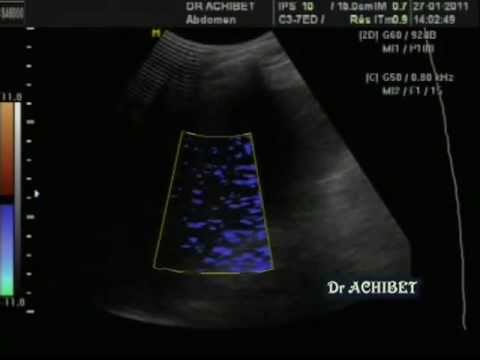

La ponction Ascite :